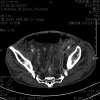

Large bowel perforation is an acute abdominal emergency requiring rapid diagnosis for proper treatment. The high mortality rate associated with large bowel perforation underlines the importance of an accurate and timely diagnosis. Computed tomography is useful for diagnosis of ingested foreign bodies, and endoscopic repair using clips can be an effective treatment of colon perforations. We herein describe a 78-year-old man with sigmoid colon perforation caused by accidental swallowing of a jujube pit. The jujube pit had become stuck in the wall of the sigmoid colon and was successfully removed by colonoscopy, avoiding an aggressive surgery. As a result of developments in endoscopic techniques, endoscopic closure has become a feasible option for the management of intestinal perforation.